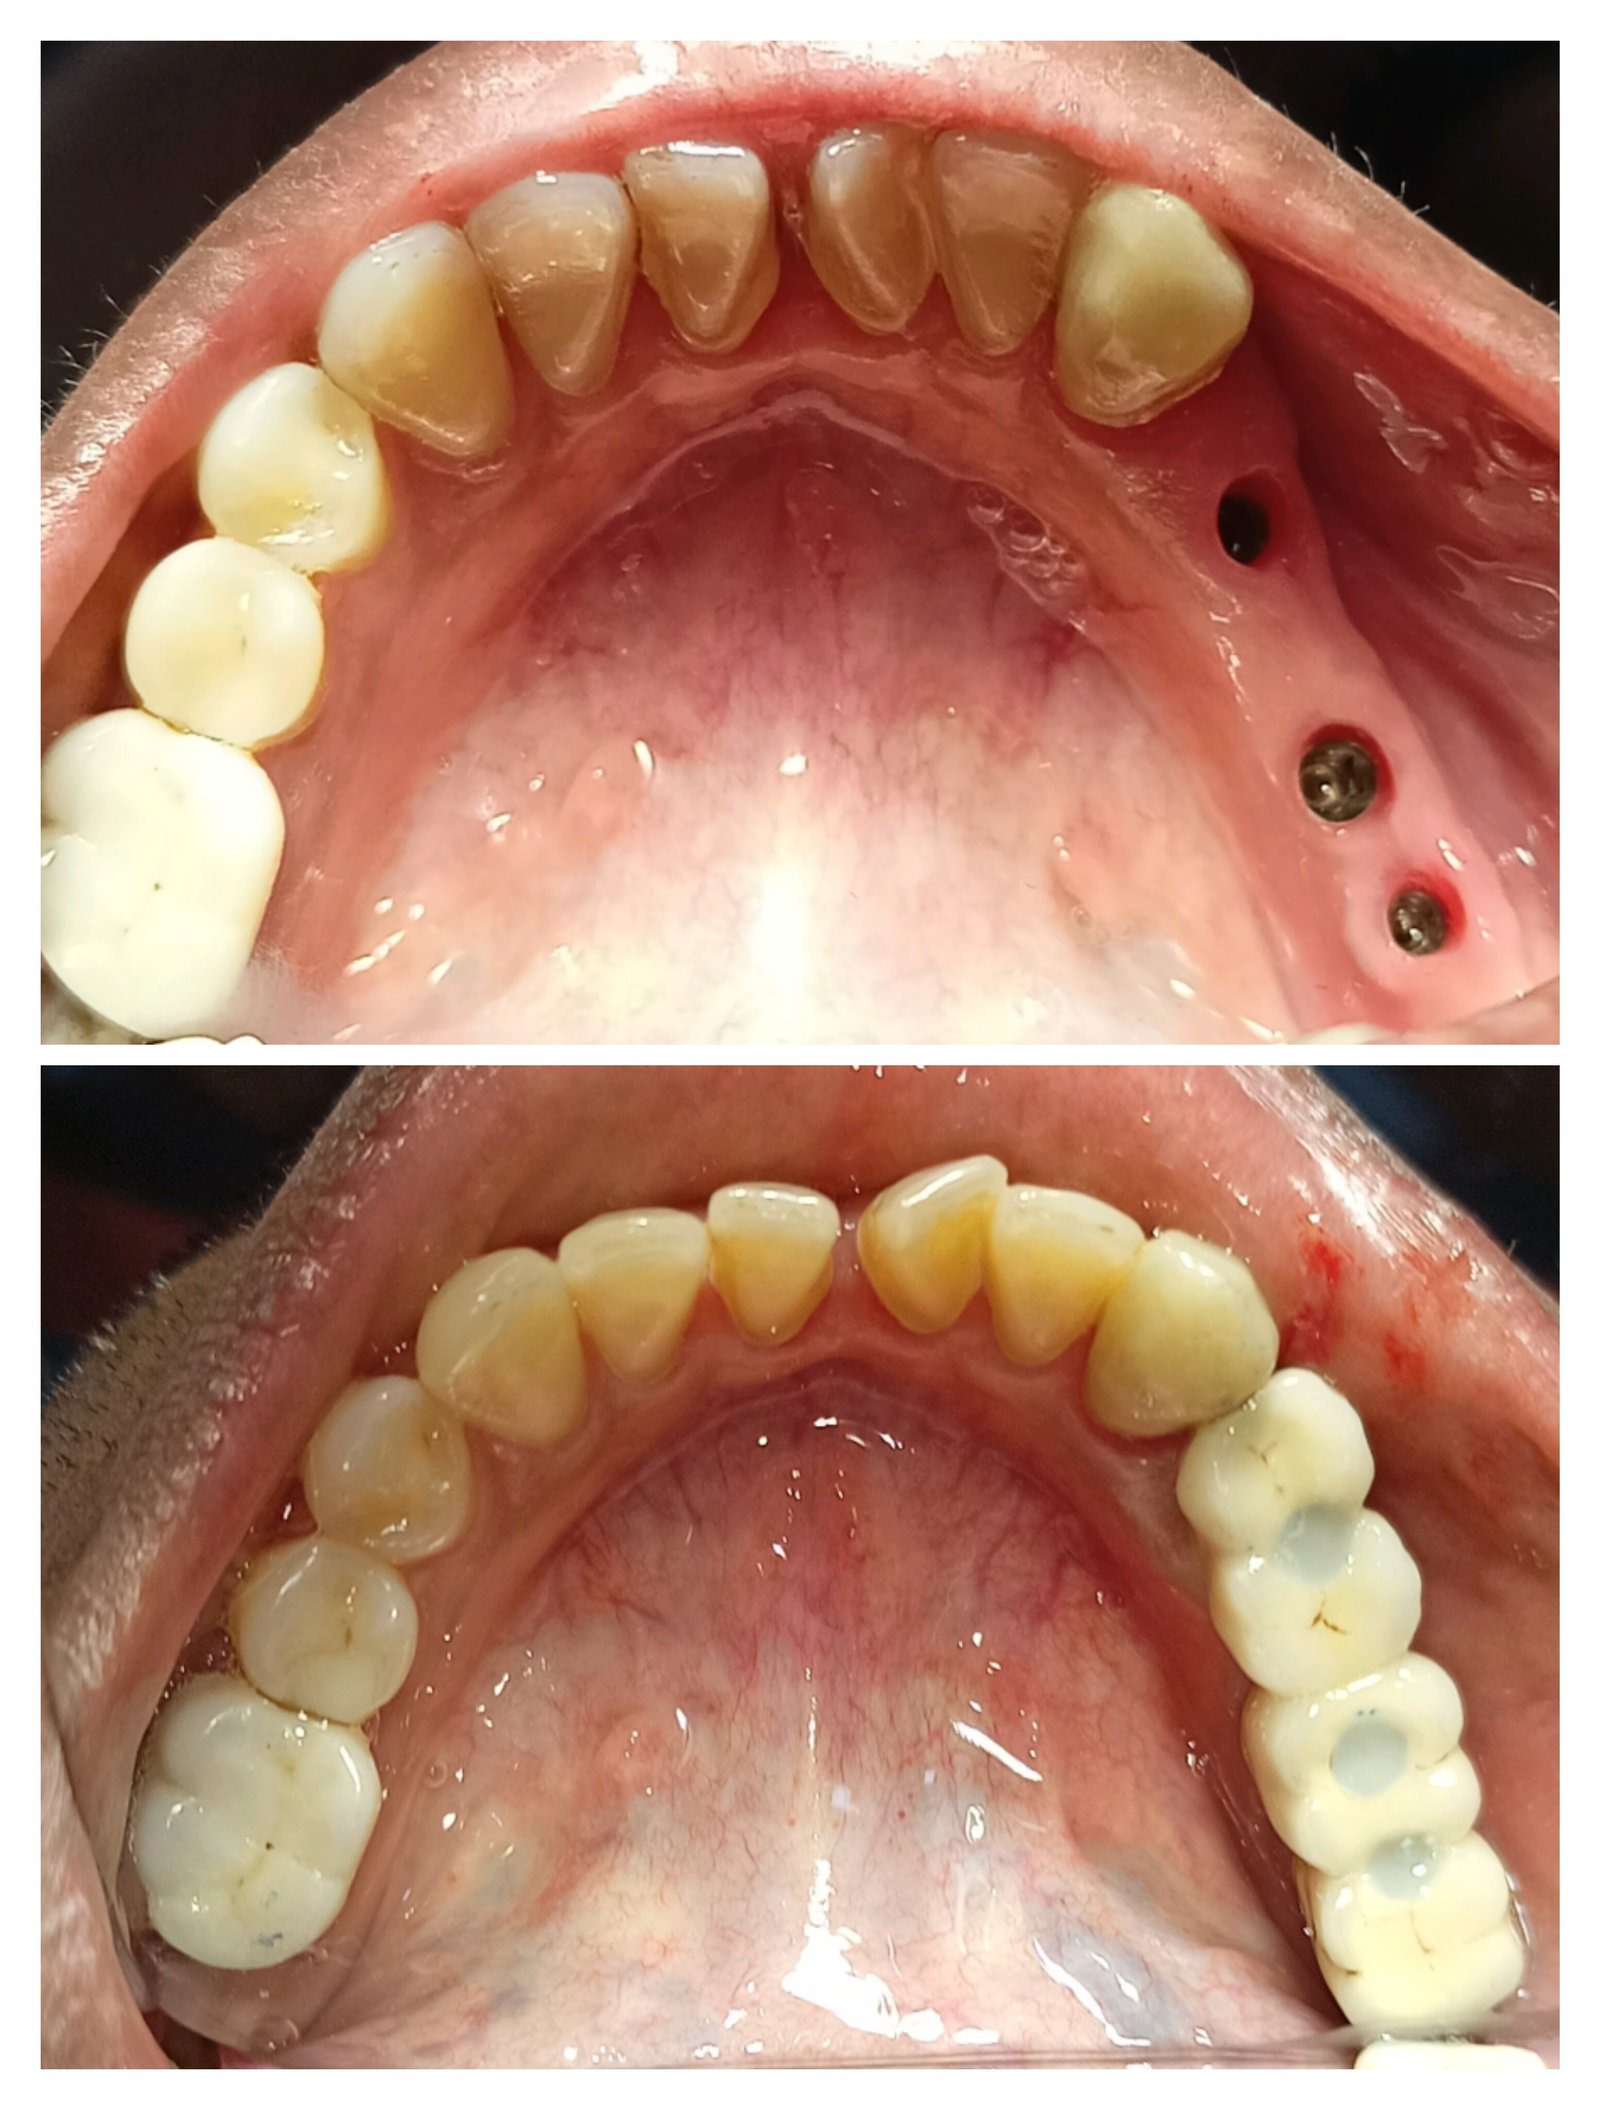

Dental Implants

Permanent replacement for missing teeth using advanced implant systems for natural look and function.

Periodontal & Implant Treatments

• Dental Implants & Implant-Supported Teeth

• Dental Implants & Teeth Replacement

• Bone Grafting for Implants